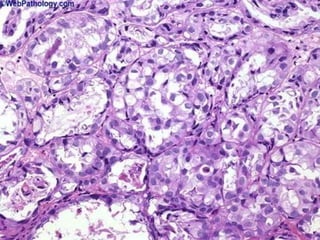

CHORIOCARCINOMA,

Just like testis or placenta

CHORIOCARCINOMA, Just liketestis or placenta